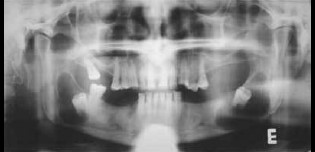

Paciente do sexo masculino de 64 anos, leucoderma, apresentando duas lesões radiolúcidas uniloculares, de bordas definidas, associadas aos dois terceiros molares mandibulares inclusos, as quais foram descobertas por meio de uma radiografia panorâmica de rotina. No exame intra-oral, o paciente não apresentava evidência de aumento de volume ou expansão das tábuas ósseas, vestibular e lingual. A radiografia panorâmica revela dois terceiros molares inferiores inclusos. Ambos se encontravam associados à lesão radiolúcida, unilocular, de bordas bem definidas. Sob anestesia local se realizou um retalho mucoperióstico vestibular ao nível do terceiro molar inferior direito, realizando a enucleacão da lesão juntamente com o dente retido. Posteriormente as bordas da ferida foram suturados com fio de seda 3-0, e as peças enviadas para estudo histopatológico. A lesão do terceiro molar inferior esquerdo foi tratada no mesmo dia sob anestesia local, realizando-se inicialmente uma punção com agulha nº 18 e seringa de 10 cc, para conhecer o conteúdo da lesão. Foi aspirado um líquido seroso amarelado contendo cristais de cálcio em seu interior. Posteriormente, uma incisão elíptica foi realizada ao nível do rebordo alveolar na região do terceiro molar e coletada parte da mucosa que recobria a lesão e encaminhada para estudo histopatológico. Finalmente, foi instalado um tubo de borracha confeccionado a partir de uma goteira, e em seguida foi fixado com fio de nylon 3-0 com ponto simples. A finalidade do tubo de borracha foi estabelecer a comunicação permanente da lesão com a cavidade bucal, com a finalidade de diminuir a pressão existente, favorecendo a neoformação óssea. O terceiro molar inferior esquerdo foi removido no mesmo ato cirúrgico. O tubo de borracha foi removido 3 semanas depois da cirurgia.

Ambos os casos os resultados histológicos confirmaram o diagnóstico clínico inicial.

Radiografia Inicial